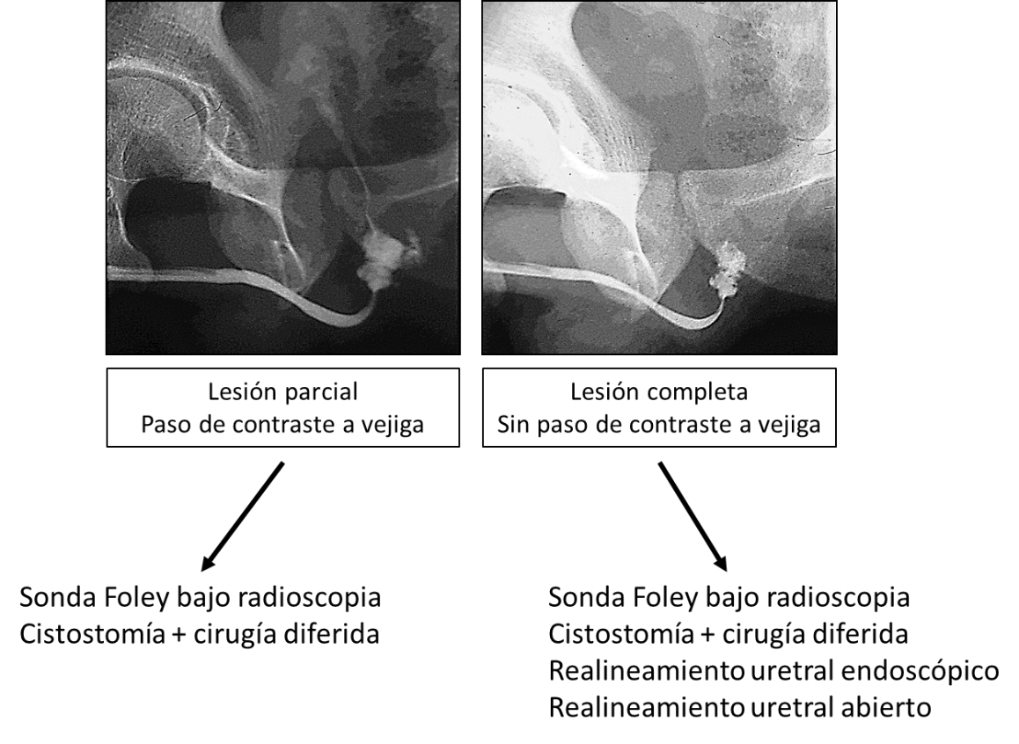

Podemos encontrarnos con 3 situaciones, que pueden objetivarse en lesiones tanto de la uretra anterior (distales al diafragma urogenital) como de la uretra posterior (a nivel o proximal al diafragma urogenital) (9,11).

- Sin extravasación de contraste: En los casos de elongación o contusión uretral superficial sin interrupción de la submucosa.

- Extravasación con paso de contraste hacia la vejiga: En las lesiones parciales.

- Extravasación sin paso de contraste a la vejiga: En las lesiones completas.

Manejo inicial de las lesiones traumáticas de la UP (9,11,12):

- Lesión parcial:

- Cateterización uretral simple: Se puede intentar la colocación de una sonda Foley, suavemente y bajo control radiológico, si es exitoso se mantiene durante 2-3 semanas y previo a su retirada se realiza una pericateterografía. Para ello, sin retirar la sonda, se introduce entre la sonda y el meato uretral, una bránula vascular 16G o 18G a través de la cual se inyecta medio de contraste. Si ya no hay extravasación del contraste, se retira la sonda. Si persiste la extravasación, se mantiene la sonda y se repite la pericateterografía semanalmente hasta su resolución.

- Cistostomía suprapúbica: Si se encuentra alguna dificultad en el cateterismo uretral, se debe suspender el procedimiento e instalar una cistostomía. A las 2-3 semanas puede realizarse una uretrocistografía combinada para determinar las características de la lesión uretral y definir su manejo diferido. Para ello, se realiza una uretrografía retrógrada y se coloca una pinza de pene para mantener el contraste en la uretra. A continuación, se llena la vejiga con 250-300 ml de contraste diluido al 50% y se autoriza a iniciar la micción, se esta manera se evalúa la continencia del cuello vesical, su apertura, la localización de la lesión uretral y su longitud.

- Otra opción es el realineamiento uretral endoscópico o abierto, indicado en pacientes en los que el cateterismo uretral no se pudo realizar y que van a ser operados por otra razón.

- Lesión completa (9,10,11):

- Cateterización uretral simple: En ocasiones también es posible la instalación de sonda uretral en las lesiones completas, siempre suavemente y bajo control radiológico. La sonda permanecerá de 3 a 6 semanas. Previa a su retirada se realizará una pericateterografía.

- Cistostomía suprapúbica: Si se encuentra alguna dificultad en el sondaje, se suspende el procedimiento y se instala una cistostomía. A las 2-3 semanas se realiza una uretrocistografía combinada para caracterizar la lesión y se programa la cirugía diferida. Esto supone aceptar un 100% de estenosis, pero la incidencia de complicaciones (incontinencia y disfunción eréctil) parece ser menor.

- Realineamiento uretral primario endoscópico: Se plantea en pacientes que van a ser operados de otras lesiones. El objetivo es intubar la ruptura, dejando instalada una sonda uretral . Se puede realizar con cistoscopio rígido o flexible, o con técnica combinada en forma retrógrada y anterógrada a través de un acceso suprapúbico. Debe realizarse cuando la situación del paciente lo permita hasta 2 semanas postaccidente. El periodo ideal es dentro de las primeras 48 horas. La sonda se mantiene por 3-8 semanas. Las tasas de éxito varían entre 70-93%, pero el problema principal es el alto índice de recidivas a largo plazo (hasta 90%) y que requieren procedimientos adicionales para su resolución. El tiempo empleado hasta la solución definitiva es mucho mayor en los casos de realineamiento endoscópico comparado con la cistostomía y cirugía diferida (122 meses vs 7 meses). Por este motivo, ante una recidiva la recomendación es la uretroplastia (13,14). Se recomienda efectuar realineamiento uretral primario si la FP compromete al sacro con daño del plexo sacro, quedando el cuello vesical abierto. En esta situación, a pesar de tener cistostomía, puede escapar orina al espacio perivesical.

- Realineamiento uretral primario abierto: Se plantea en pacientes que van a ser sometidos a una laparotomía exploradora. Se accede a la vejiga, abriéndola longitudinalmente, se explora y si es posible se realiza la intubación uretral usando técnica combinada (retrógrada y anterógrada). No se debe explorar el hematoma prevesical ni disecar el espacio retropúbico.